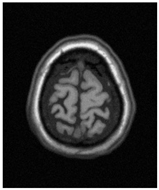

In Figure 3, we can see that the boundary in the bottom right around the white matter stays stable when threshold changes from 100 to 105, but those around the gray matter (GM, shown in the cyan bounding box) change significantly. Furthermore, when the threshold changes from 105 to 110, the boundaries inside the GM change significantly. Both the situations show that those boundaries near the truth of tissue boundaries may possess higher stability as the thresholds change.

Figure 3.

Edges of the thresholding result. (a) Top left: 100; top middle: 105; top right: 100 (blue), 105 (red); bottom: local thresholding result of the region in the cyan box with 100–105 and the heatmap at the rightmost; (b) top left: 105; top middle: 110; top right: 105 (blue), 110 (red); bottom: local thresholding result of the region in cyan box with 105–110 and the heatmap at the rightmost. (The heatmap was generated as follows: As the threshold varies, superimpose the boundary pixels and increase the pixel count by one each time. The pixel with the highest count is set to the darkest blue. Thus, the darker a boundary pixel is, the more stable it is).

To the best of our knowledge, there are few intensity-based methods that consider pixel-wise edge stability. Li [56] evaluated shape stability with the region expanding rate (RER) and selected a threshold with a low RER; Serena [57] considered the area-stable elongation to find the stable region. All of the above methods measured an overall stability pattern between boundaries. In fact, pixels on the edge possess different stability values, as Figure 3 shows. Therefore, we can conclude that pixels on the edge possess stronger stability.